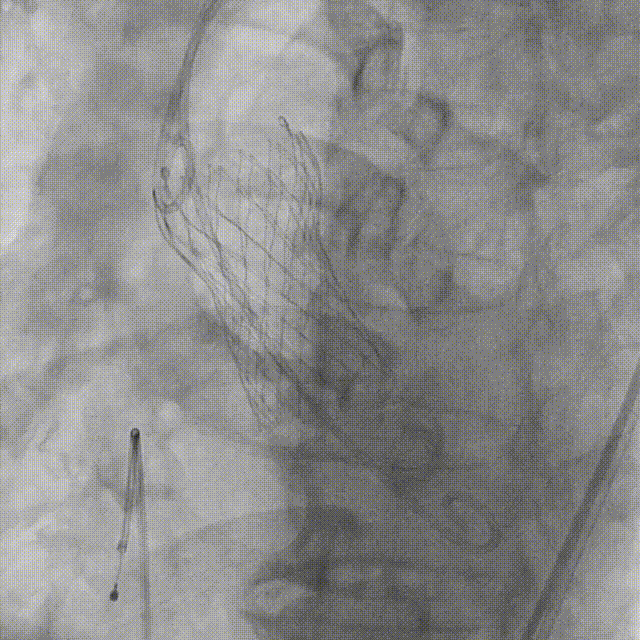

Evolut PRO 为美敦力第三代产品,具有高生存率、低卒中率、极少瓣周漏以及优秀血流动力学特性。秉承经典环上瓣设计理念,增加稳定多次可回收功能和生物组织外裙边,大大提高手术安全性和成功率,带给患者更好临床获益。

5. 植入26mm Evolut PRO瓣膜

本例患者为78岁老年男性,而功能性二叶瓣,钙化极重,右无间、左无间均见钙化融合,无冠瓣钙化向下延伸至LVOT,左冠开口高度偏低。经过团队综合评估,美敦力EvolutPRO瓣膜具备Cusp Overla和Commissural alignment 技术, Cusp overlap技术可减少起搏器植入率,Commissural alignment技术可以避免瓣膜接缝挡住冠脉开口,减少未来PCI通路阻挡的风险。同时合适的径向支撑力在瓣环重度钙化并延申到LVOT约8mm的情况下更能稳定锚定,13mm高度猪心包生物外裙边可以减少不规则瓣环瓣周漏,且拥有稳定的多次(3次)可回收功能,避免术中瓣膜移位带来的风险,最终选用26mm的Evolut PRO瓣膜。采取经右股动脉极简式TAVR策略,不全麻、不插管、无导尿、无食道超声。经过吴永健团队熟练配合,瓣膜位置合适,无明显瓣周漏,达到预期效果,患者术恢复良好。